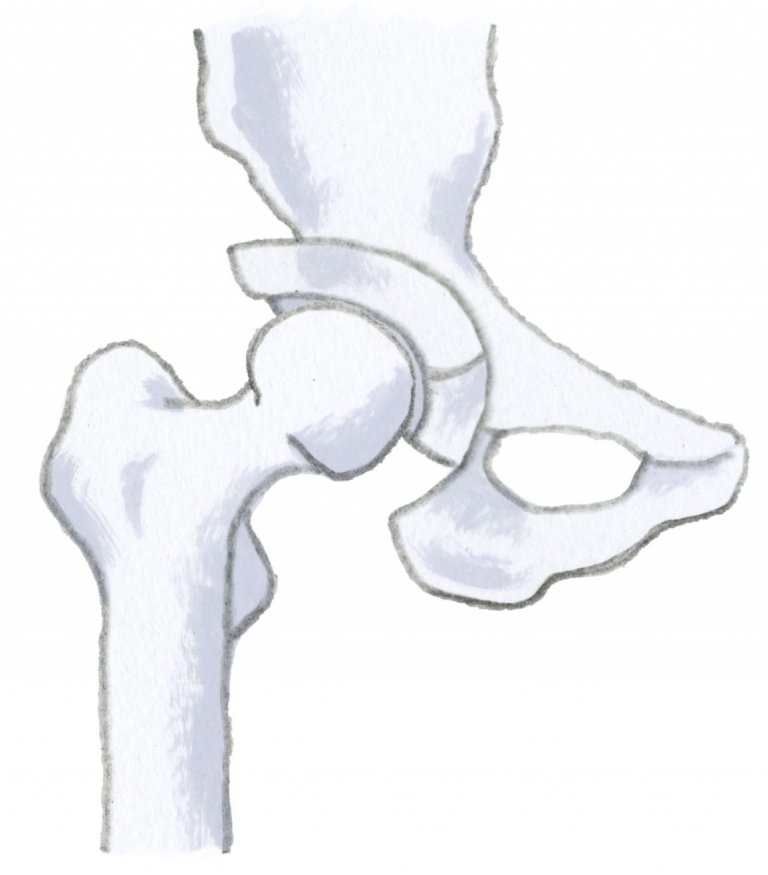

股関節の特徴は、専門的には「球関節」といわれる形にあります。野球の球と同じ意味で、まん丸という言う意味です。球関節の代表は、肩関節と股関節です(図1)。どちらも、真ん丸の関節ですので動く範囲がとても広くなっています。また、股関節は立っている・歩いているときにとても大きな重みがかかります。歩いているときは、体重の3~4倍の重さが股関節にかかります。そのため股関節は、軽微な障害でも強い痛みと動きの制限が生じやすくなっています。

図1 股関節の特徴「球関節」